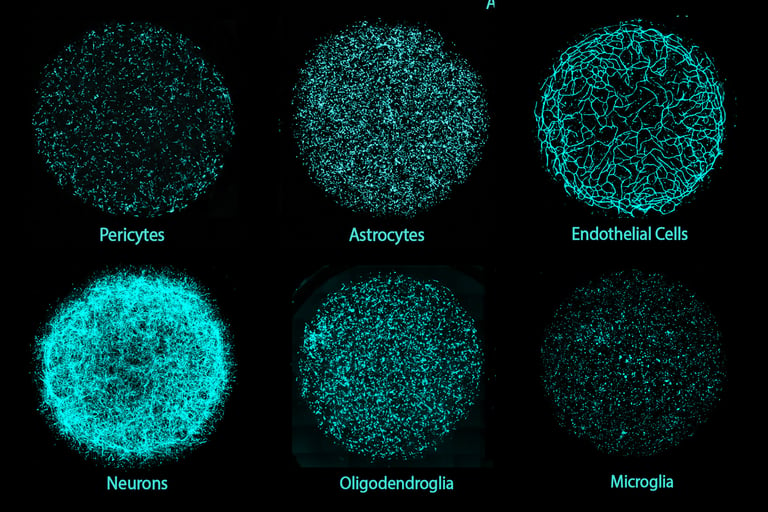

Researchers at MIT have developed an innovative 3D human brain tissue platform called Multicellular Integrated Brains (miBrains), which includes all six major brain cell types, such as neurons, glial cells, and vasculature, in a single culture to advance brain research and drug development.

These miBrains are created from induced pluripotent stem cells derived from individual donors, enabling customization through gene editing and supporting large-scale studies by mimicking essential features and functions of human brain tissue.

The model combines the benefits of lab-grown cell cultures and animal models by offering cellular complexity, rapid production, genetic personalization, and features like blood vessel formation, immune defenses, and nerve signal conduction, including a functional blood-brain barrier.